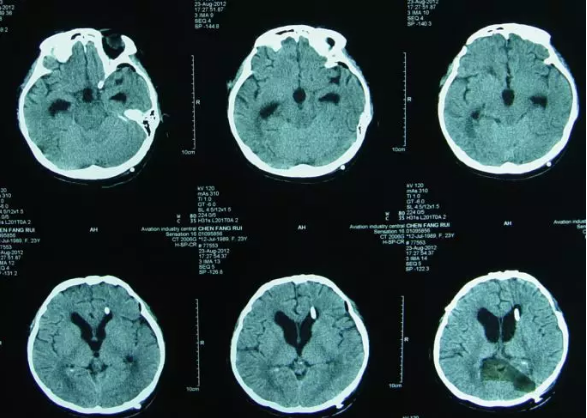

但内镜造瘘术后2小时出现了癫痫发作,意识模糊,查头颅CT:内镜造瘘术后状态,双额部硬膜下血肿(图-1)。

图-1:2012年4月28日头CT

内镜造瘘术后当天再次开颅进行了硬膜下血肿清除术,并留置右侧侧脑室外引流管,术后患者意识变清,查头颅CT:血肿基本消失(图-2)。

图-2:2012年4月28日开颅术后头CT

内镜造瘘术后第2天即2012年4月30日,行头颅CT:“三脑室内缩小”(图-3),进行腰穿检查颅内压为170mmH20,随拔除脑室外引流管。

图-3:2012年4月30日头CT